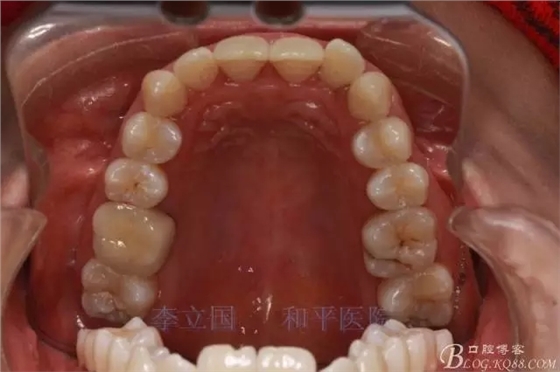

患者主訴前突。

矯治方案:

1.拔除14、24、31。

2.Damonclear排齊整平。

3.微種植支抗內(nèi)收上下前牙。

4.調(diào)整咬合關(guān)系。

5.保持。

治療要點(diǎn):

1.患者上前牙直立,面型前突,典型的嘴凸牙不吐,關(guān)鍵是前牙轉(zhuǎn)矩控制,建議使用高轉(zhuǎn)矩托槽。

2.磨牙關(guān)系一側(cè)完全遠(yuǎn)中,一側(cè)遠(yuǎn)中尖対尖,采用兩個(gè)上4,一個(gè)下1的拔牙模式。

3.上頜應(yīng)用支抗釘。表麻下在56牙槽間隔植入,注意因使用的為鈦合金釘,一直保持植入角度與骨面成60度角,不要垂直植入再改變角度。要求即刻加載,即刻加載力值2盎司。

4.使用長(zhǎng)牽引鉤,使?fàn)恳咏项M骨阻抗中心,防止上頜骨的順時(shí)針旋轉(zhuǎn)。

5.回收過程中,上下前牙輕搖椅,防止覆合加深。